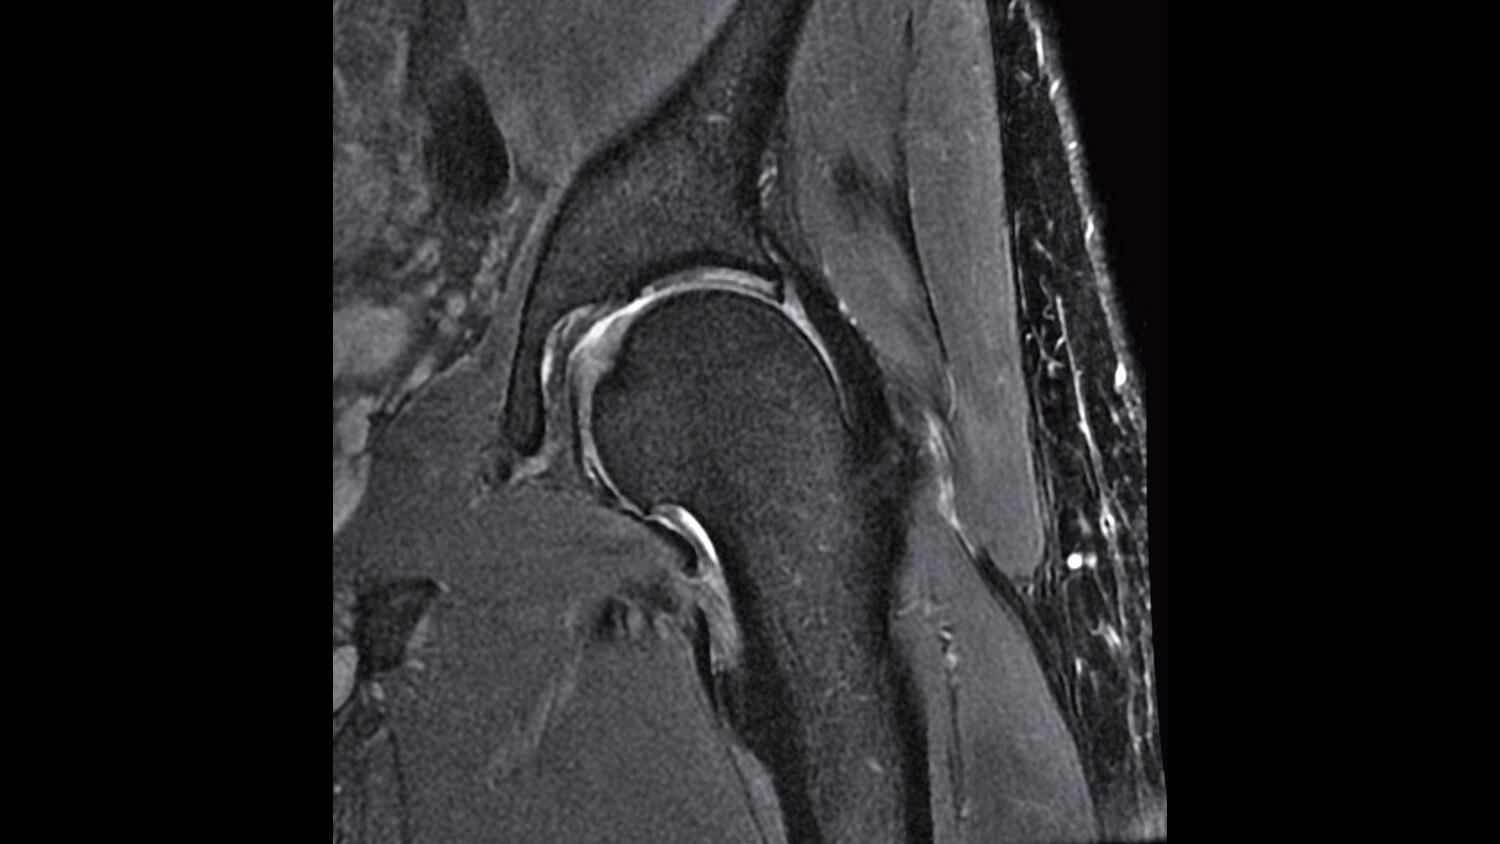

A large usable field of view is needed to properly image off-center anatomy such as a shoulder or hip. So the Discovery* MR750w features a 70 cm flared, open bore design with a large 50 x 50 x 50 cm field of view.

Gradients and RF body coils are water and air-cooled for optimum duty-cycle performance, short repetition time (TR) and echo time (TE), producing sharp and clear images.